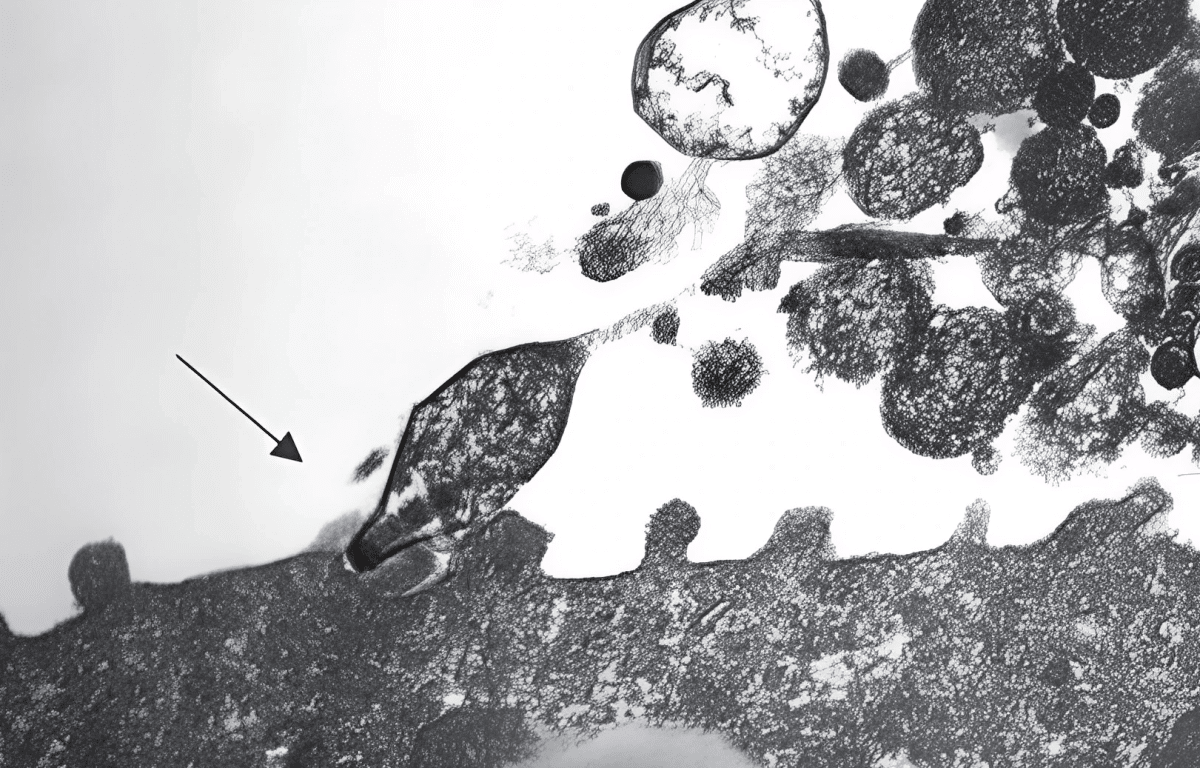

Mycoplasma pneumoniae под микроскопом / © Kevinjesusmontoyadelcampo, ru.wikipedia.org